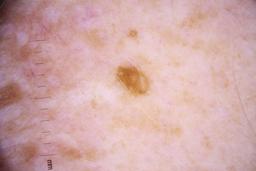

ISIC_4077341

Clinical

| Field | Value |

|---|---|

| acquisition_day | 1 |

| age_approx | 50 |

| anatom_site_1 | Trunk |

| anatom_site_2 | Anterior trunk |

| concomitant_biopsy | False |

| dermoscopic_type | contact non-polarized |

| diagnosis_1 | Benign |

| diagnosis_confirm_type | serial imaging showing no change |

| family_hx_mm | False |

| image_type | dermoscopic |

| lesion_id | IL_9238622 |

| patient_id | IP_1969685 |

| personal_hx_mm | True |

| sex | male |

Columns

Showing first 50 images.